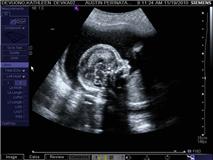

What an amazing day! Kenny and I were off to see Dr.B who ended up being Catherine the R.N. Check out some of the pictures Kenny was able to purchase.You know Kenny didn't hesitate on that purchase :)

Little did we know Finshep is actually 20 weeks and 1 day old today. Apparently we time traveled right past our big 5 month marker! And get this... our corrected due date?? April 7th! Carla's birthday, the day I've been sure that baby would be born. I guess we'll see. Oh and as of right now, your guess is as good as ours :)